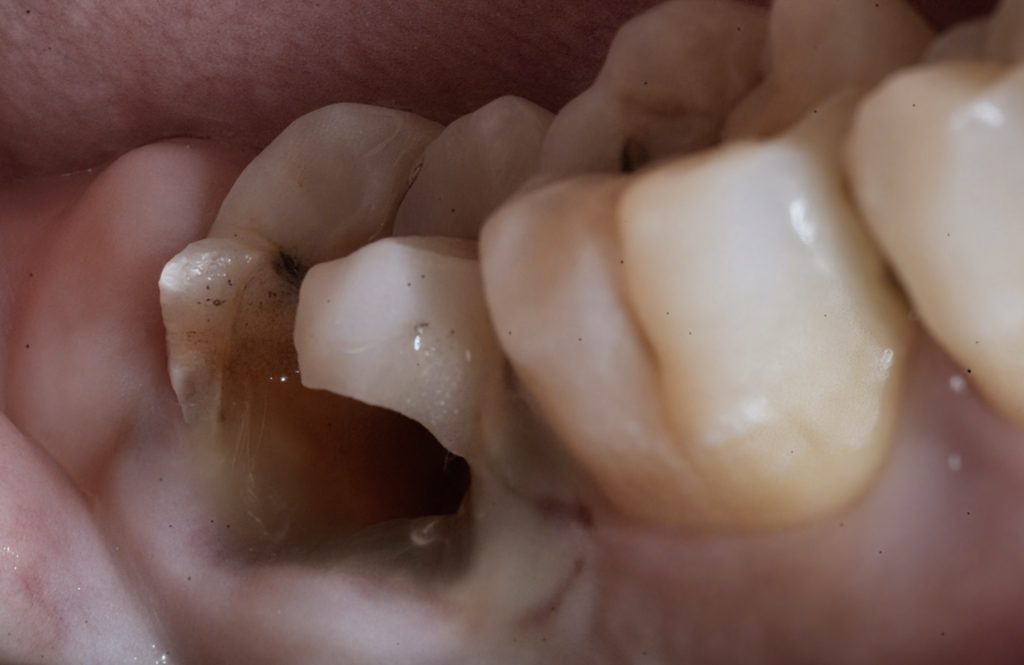

Clinical and radiographic evaluation showed a large Class V lesion extending below the CEJ with pulpal involvement and secondary dentin sclerosis (Fig 1 & 2).

1️⃣ Pre-operative view showing deep Class V caries

2️⃣ Pre-op radiograph